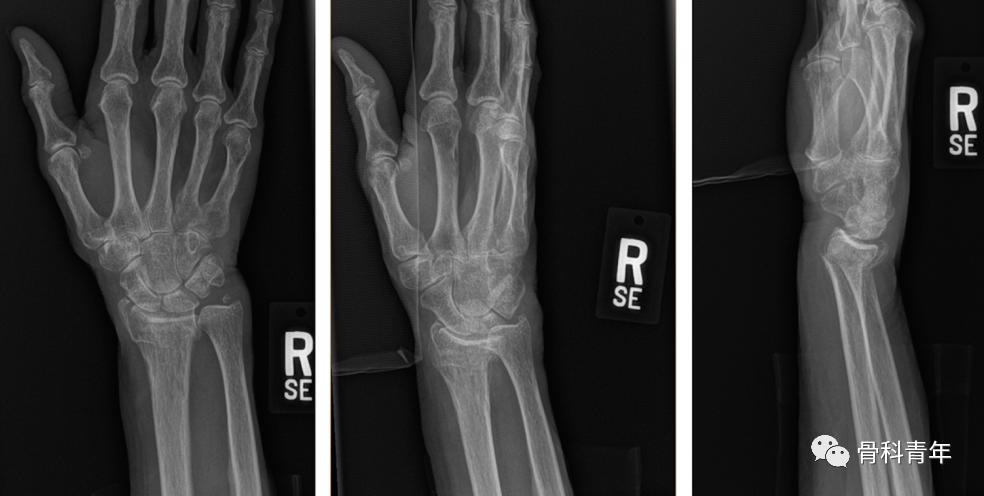

掌侧锁定加压接骨板(Volar locking compression plate,LCP)内固定是桡骨远端骨折治疗的金标准,但LCP并非对所有桡骨远端骨折均实用,如桡骨极远端骨折、背侧缘骨折、掌侧die-punch骨折等;同时,LCP钢板也存在较多的并发症,包括旋前方肌损伤、骨折血运破坏、掌侧软组织激惹、背侧肌腱磨损等,同时对严重骨质疏松患者存在较高的内固定失效风险。

对降低术后并发症和减少医源性损伤的需求,催生了各种新型内固定方式的发展。本文简要介绍4种新型内固定方式,供临床医生参考。

一、桡骨远端髓内钉

髓内钉技术广泛应用于长骨骨干骨折,闭合或有限切开复位有效降低医源性因素对血运的破坏,并具有良好的轴心固定生物学优势。桡骨远端髓内钉出现较晚,该技术适用于完全关节外骨折及简单的关节内骨折,对关节内粉碎骨折并不适用

桡骨远端骨折髓内钉固定的前提是闭合复位效果满意,克氏针临时固定后,通过桡骨茎突开口,自腕背侧第1/2间室间隙进入。该技术存在潜在的损伤包括桡神经分支损伤,螺钉穿入下尺桡关节或桡腕关节等。

二、Cage支撑技术

Cage支撑技术广泛应用于骨质疏松性骨折的复位固定,如肱骨近端骨折等。同理,该技术也可应用于骨质疏松性桡骨远端骨折。理论上,在最小的软组织剥离情况下,复位后经有限切口置入Cage支撑,实现髓内支撑及有效的软骨下支撑,并辅助螺钉固定。但该技术对骨量条件良好患者可能并不适用,且内植物取除困难。

三、PEEK锁定钢板

PEEK钢板存在以下特性:① 透视下不显影,利于术中观察骨折复位情况及评估骨折愈合情况;② 与骨皮质弹性模量相近,避免应力遮挡效应;③ PEEK材料与金属螺钉,避免冷焊接。但同时,PEEK钢板不显影技术不利于评估内固定是否失效,且PEEK钢板无法应对塑形,在改变螺钉方向后内固定强度减弱。

四、桡骨远端关节置换

关节置换用于严重关节内粉碎骨折的治疗已应用于肱骨近端骨折、肱骨远端骨折、胫骨平台骨折等。同理,关节置换也可用于桡骨远端骨折。适用于严重粉碎性、关节内、骨质疏松性骨折的一期治疗,或内固定失效的二期翻修。通常采用桡背侧切口,自第3/4间室间进入。